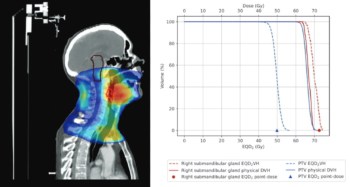

Read article: Clinical implementation of RadCalc’s automated 3D collapsed cone secondary dose check

Clinical implementation of RadCalc’s automated 3D collapsed cone secondary dose check

Live webinar on 21 February 2022 exploring RadCalc’s 3D collapsed cone module